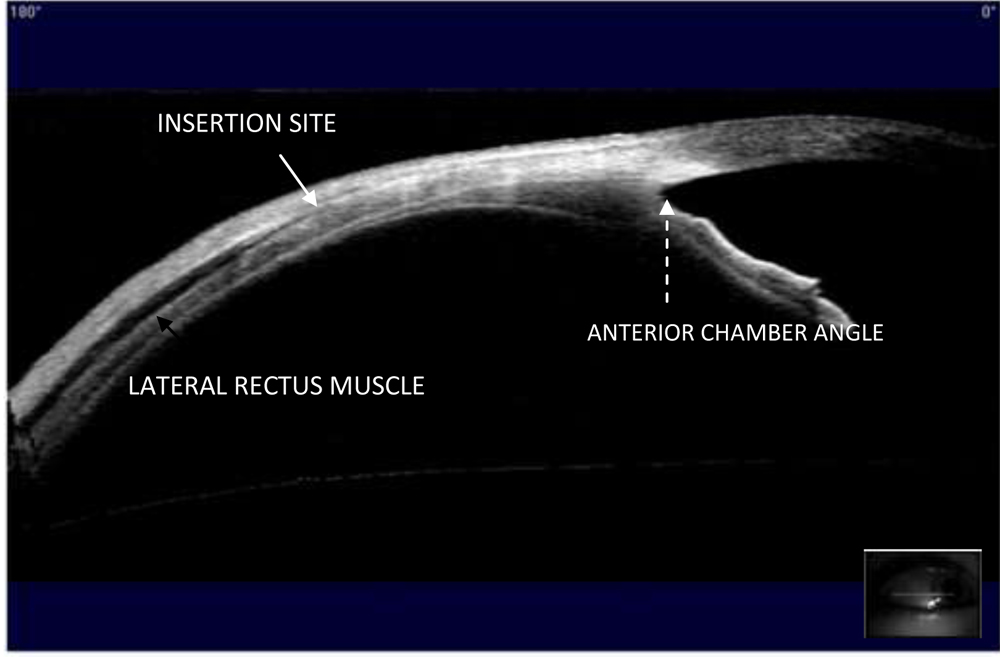

In the cross-section image, the end of the cleft between the muscle and sclera was defined as the insertion site.

Figure 1. AS-OCT image of a muscle for primary surgery. The lateral rectus muscle of the right eye is imaged. Inset shows the position of the eye and the orientation of the scan.

However, the corneoscleral limbus is difficult to determine in AS-OCT images. The iris root (the anterior chamber angle) lies approximately 1.0 mm posterior to the limbus in the horizontal meridian3. With the help of the caliper function in the AS-OCT software, we placed the calipers on the perpendicular projection of iris root on the corneoscleral surface and on the muscle insertion site to measure the angle-insertion distance. The actual value of limbus-insertion distance was adjusted by adding an additional 1.0 mm to the angle-insertion distance. Five consecutive readings were taken, and the mean value was taken for analysis.